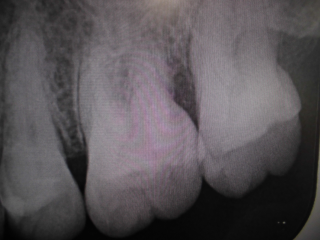

左上奥歯が割れています。一般的なレントゲンではわかりません。

CTでは破折線がはっきり見えます。患者様も納得しやすいです。